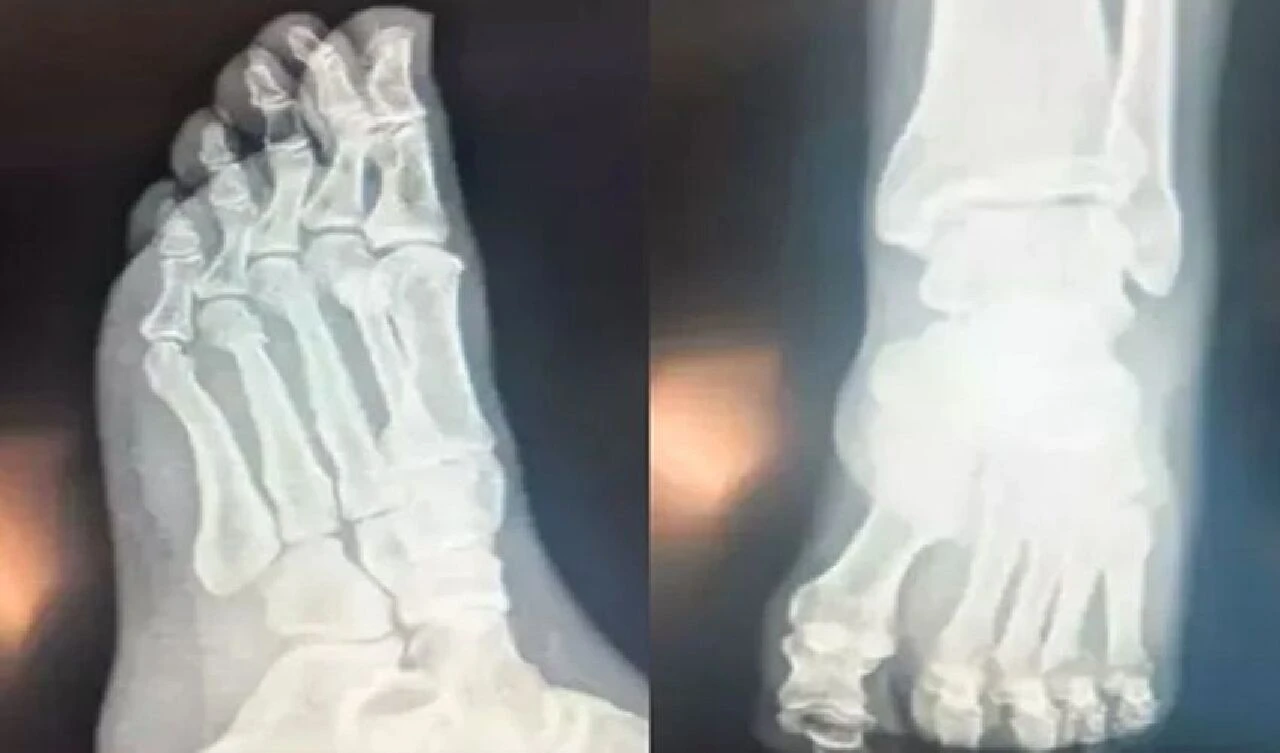

CHP Genel Başkanı Özgür Özel’in “Herkes inceleyebilir” dediği filmleri inceleyen Ortopedist Prof .Dr. Tarık Yazar, "Özel’in röntgen filmlerini incelediğimizde parmak kemiklerindeki kırıkları gördüm. Açık bir yara olmaması bir şanstır. Yani, dışarıya kan akmamış." dedi.

Röntgende yara olup olmadığı her zaman görülmez. diyen Yazar "Ancak, Özgür Bey’in röntgenini incelediğimizde yine de şanslı olduğunu gördüm. Biz buna ‘şanslı kırık’ deriz. Aslında tam kırık da diyemeyiz. Ayrılmamış, kemiğin özelliği bozulmamış. İyileşme yeteneğinin fazla olduğu bir bölgede kırık var. Şanslı tarafı kanlanmanın kuvvetli olduğu bir bölgede kırık gördüm. Bilgisayarlı tomografiyle takibi uygun olur. Tedaviye doğru başlanmış. Mutlaka iyileşecektir. Kullandığı ayak desteği gayet doğru bir seçim. Üç aya kalmaz tam iyileşme gerçekleşir." ifadelerini kullandı.